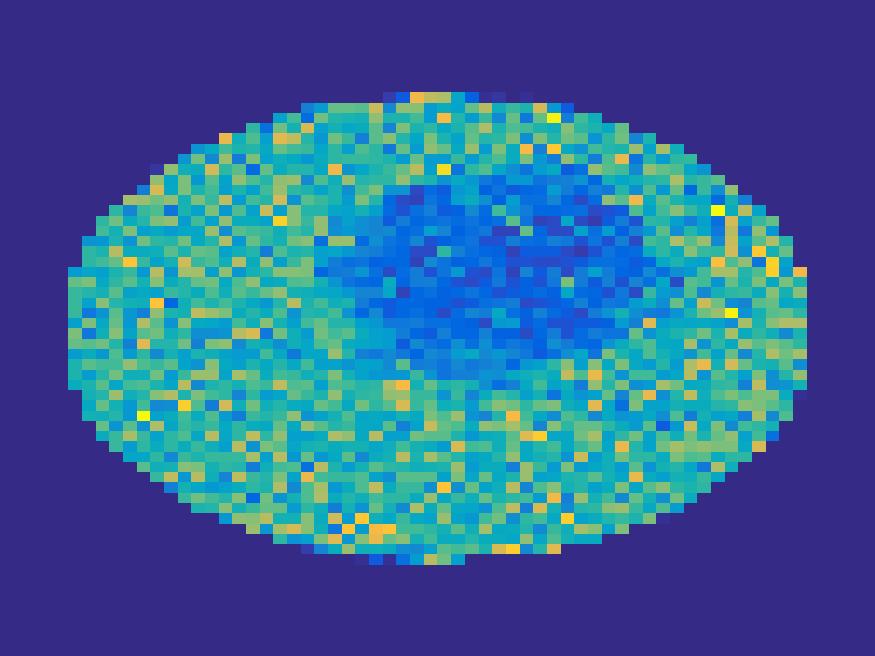

Figure 8 and 9 show the results of the ellipse and rat phantom with Poisson noise. Since the number of projections is very limited and the corruption by Poisson noise, the reconstruction by both FBP and EM (with updating basis) are not satisfactory, while the proposed method is capable to reconstruct the main structure of the images faithfully.

| Frame 1 | Frame 11 | Frame 21 | Frame 31 | Frame 41 | Frame 51 | Frame 61 | Frame 71 | Frame 81 |